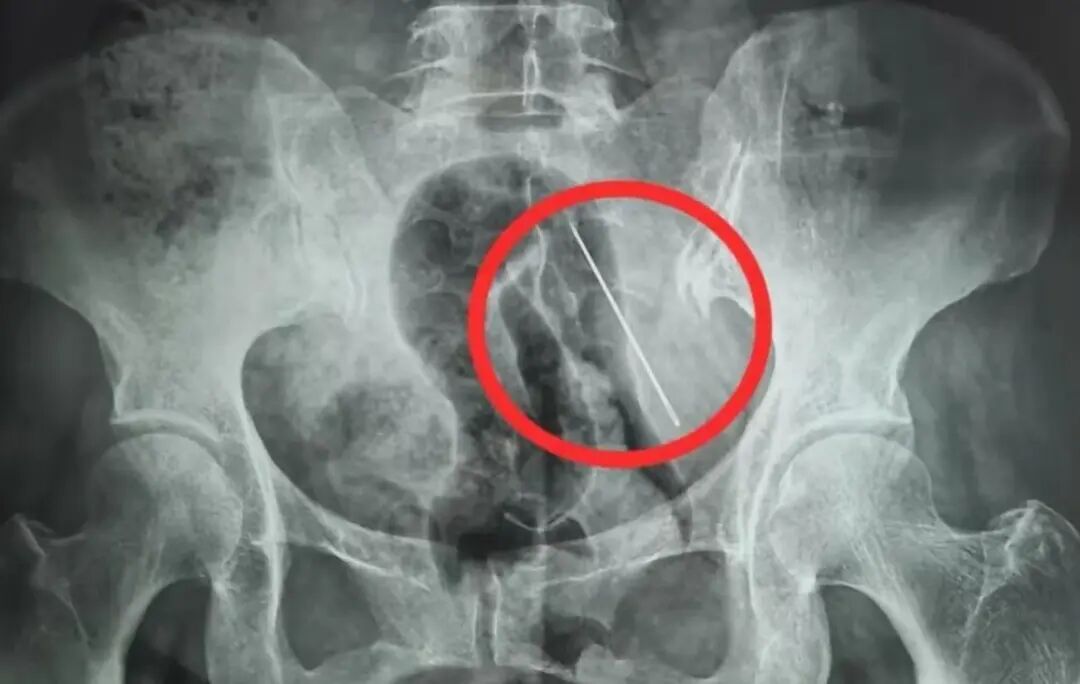

X光片显示张某腹部内有异物(医院供图)

接诊后,急诊科当即安排张某进行腹部CT和X线检查。检查结果显示,她的腹壁内有一根长4厘米的异物。经研判,这根缝衣针只是扎入脂肪层内,并未穿透掉入腹腔。